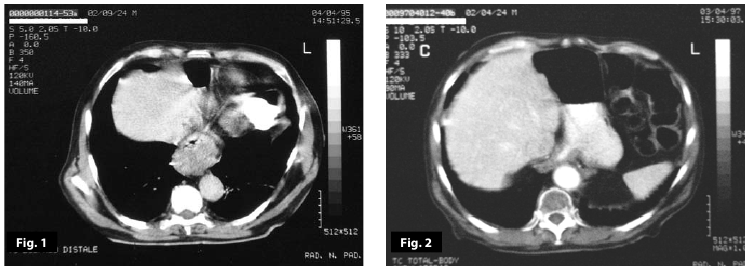

Figure3-4

Figure1-2-3-4